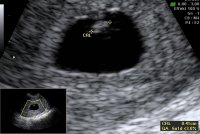

Alt såg bra ut, og var komt like langt som forventetEr så letta! 7+4 og hjerterytme på ca 155

Aww, h*n ser ut som en liten bamsemumsLillegull! Alt bra og målene stemmer perfekt med 8 uker. Sterke hjerteslag

dagene fram til 9. august kan ikke gå fort nok!Lillegull! Alt bra og målene stemmer perfekt med 8 uker. Sterke hjerteslag

Så utrolig tydelig bilde! GratulererLillegull! Alt bra og målene stemmer perfekt med 8 uker. Sterke hjerteslag